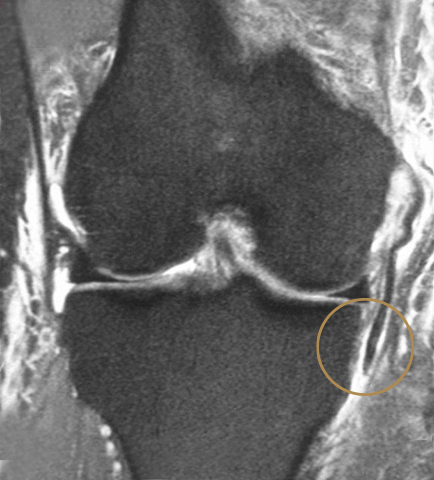

Bei Grad 3-Rupturen (siehe Bild unten) kann es vorkommen, dass sich die gerissenen Bandanteile zum Teil zurückziehen und evtl. in nicht anatomischer Position vernarben. Dies kann eine chronische Instabilität zur Folge haben. Manchmal kann dadurch die Wiedererlangung der Sportfähigkeit beeinträchtigt werden.

Bild 2: Ruptur 3. Grades am Innenband des Knies